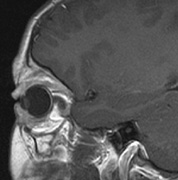

Intracranial leptomeningeal capillary vascular malformation (Figs. 21 and 22) is associated with seizures and contralateral neuromuscular weakness. Central nervous system involvement correlates highly with ipsilateral involvement of the V1 dermatome by a PWS.208,218

Fig. 22. Axial T2-weighted (a) and coronal T1-weighted (b) images of a 16-year-old boy with a port-wine lesion over the right side of his face. The right hemisphere is markedly atrophic and abnormal draining veins are seen within the right lateral ventricle (arrowheads). (c, d) The entire right hemisphere is covered by an enhancing pial angioma and the choroid plexi are enlarged. Enhancing retinal angiomas (arrows), typical of Sturge-Weber syndrome, are seen in (d).